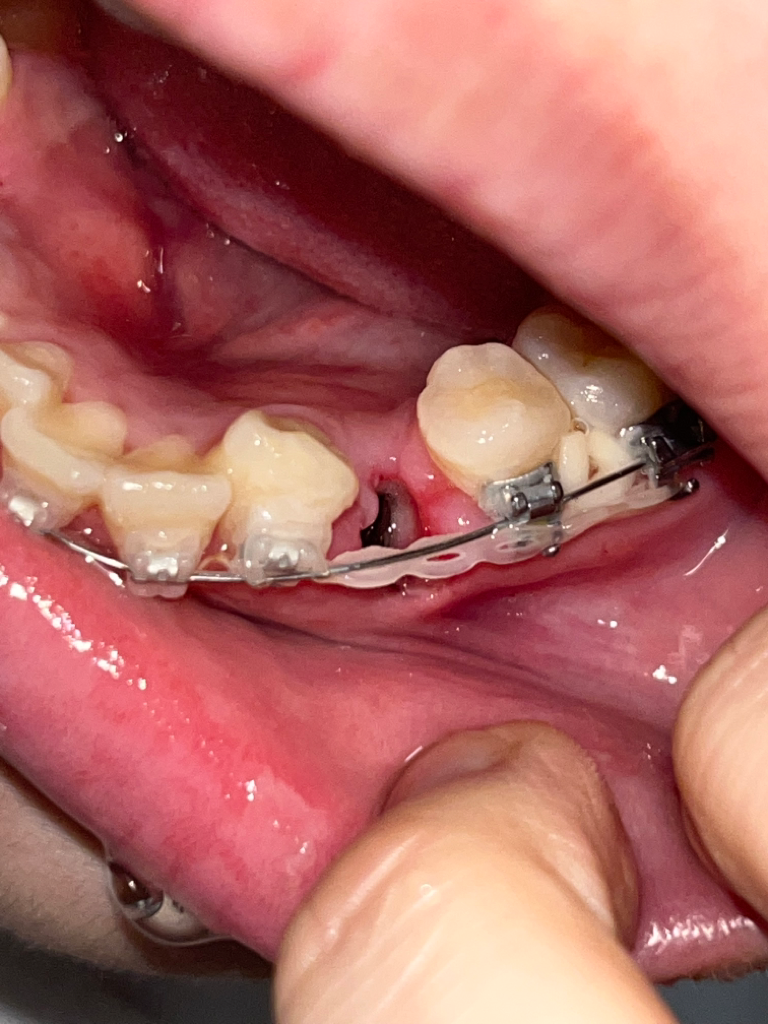

교정발치 3일차 드라이소켓인가요 ㅠㅠ

아플때마다 진통제 먹으면 괜찮아집니다 ㅜㅜㅠㅠ 근데 오늘 조심히 먹는다고 라면 먹긴했는데 그것때문일까요 ㅠㅠ?? 갑자기 어느순간부터 입안에서 역한맛이 나더니 악취가 심하게 나더라고요 드라이소켓일까요?? 병원 바로 가는게 낫겠죠?

• 2번 째 사진

사진 상 애매하기는 합니다. 통증이 극심하고 냄새도 심하게 난다면 치과를 가시는 게 좋겠습니다.

사진으로 봤을 경우에는 발치한 후에 생겨야 할 혈병이 제거된 것으로 보입니다 혈병을 제거되었을 경우 내부의 이물질이 쉽게 들어가기 때문에 냄새가 날 수 있으며 드라이 소켓이라면 해당 부의 통증이 심할 것으로 생각됩니다.

통증이 심하고 혈병이 없으며 악취가 난다면 드라이 소켓일 가능성이 있기 때문에 치과에서 진료를 받아 보는 것이 좋습니다.